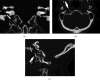

Introduction: The authors report a rare cause of isolated hypoglossal nerve palsy caused by a high cervical osteophyte. This case increases clinical knowledge of an underreported condition and teaches the clinician radiologic pearls in making the diagnosis. To their knowledge, this is the first case report showing surgical remediation of this condition. Symptoms and Clinical Findings. A 73-year-old female presented with several months of occipital headache, progressive dysarthria, dysphagia, and tongue deviation to the right. Her neurologic exam was significant for atrophy of the right hemitongue with tongue fasciculations. On protrusion, her tongue deviated rightward. Diagnosis and Therapeutic Intervention. Careful review of her initial head computed tomography (CT) imaging revealed that a high cervical osteophyte caused unilateral, isolated hypoglossal nerve palsy. Neurosurgery performed a right, far lateral approach for decompression of this osteophyte and over the ensuing months her symptoms improved.

Conclusion: High cervical osteophyte is an underrecognized cause of isolated hypoglossal nerve palsy. The imaging investigation should be systematic and focus on the skull base with magnetic resonance imaging (MRI) or CT. This is a rare occasion when high resolution CT of the skull base can actually be the more helpful imaging modality. As shown in this case, an osteoarthritic cause can be surgically ameliorated.